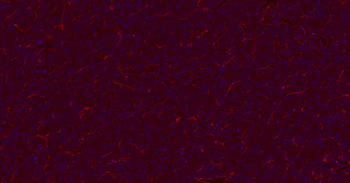

IF analysis of mouse lung tissue using anti-CD31 (dilution of primary antibody at 1:200)